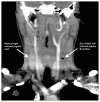

Lemierre syndrome: early recognition and management